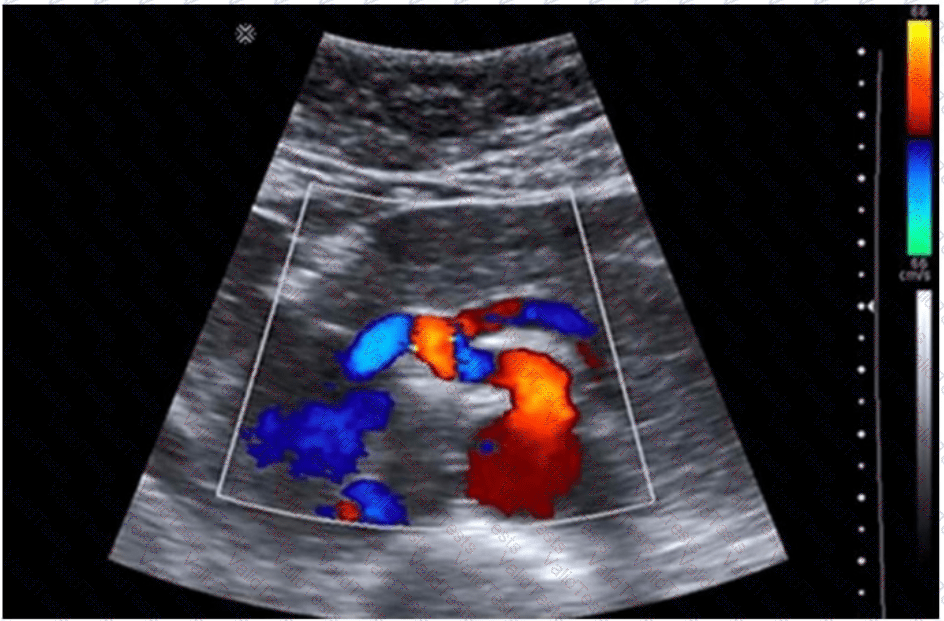

The image provided is a color Doppler ultrasound scan of the abdominal aorta and its major branches. In the center of the image, just anterior to the aorta, we see the superior mesenteric artery (SMA) arising in the sagittal plane. This is the critical area for Doppler sampling in a patient with symptoms suggestive of mesenteric ischemia.

Severe postprandial pain in a young woman may be a manifestation of median arcuate ligament syndrome (MALS) or chronic mesenteric ischemia. Both of these conditions are assessed via Doppler sampling of mesenteric vessels, specifically:

The origin and proximal segment of the SMA

The celiac artery (especially for MALS)

Doppler waveform analysis should assess:

Peak systolic velocity (PSV): >275 cm/s suggests ≥70% SMA stenosis

Angle correction should be aligned properly

Sampling must be performed at the narrowest origin point (as shown in the image)

This type of Doppler interrogation is typically done in both fasting and postprandial states to evaluate changes in flow and symptom correlation.

The SMA is anterior to the aorta and travels inferiorly into the mesentery.

The site shown in the image is ideal for measuring PSV and evaluating for stenosis or extrinsic compression.